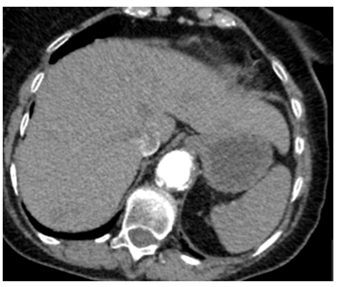

Three months later, she was presented to her general practitioner with vaginal bleeding and was evaluated in two weeks at the Gynecology clinic where on examination, a craggy 2-3cm mass, replacing the left Bartholin’s gland in the lower 1/3rd of vagina and vulva, was noted. This mass was biopsied which showed metastatic clear cell renal carcinoma. On a repeated contrast-enhanced staging CT chest, abdomen and pelvis, progression of her metastatic disease with an increase in the size of her left renal lesion to 7cm was observed (Figure 3&4). The patient was also noted to have become progressively thrombocytopenic. She was therefore, continued on the palliative care pathway with supportive treatment. At the time of submission of this article, patient was still alive under the care of the Oncologists who had discussed and commenced palliative Pazopanib at a reduced dose of 400mg daily. The patient’s main issue was bilateral lymphedema with not much symptoms from her vulvo-vaginal metastases.

Figure 4: Repeat stating CT chest, abdomen and pelvis showing progressive metastatic disease in August 2016.